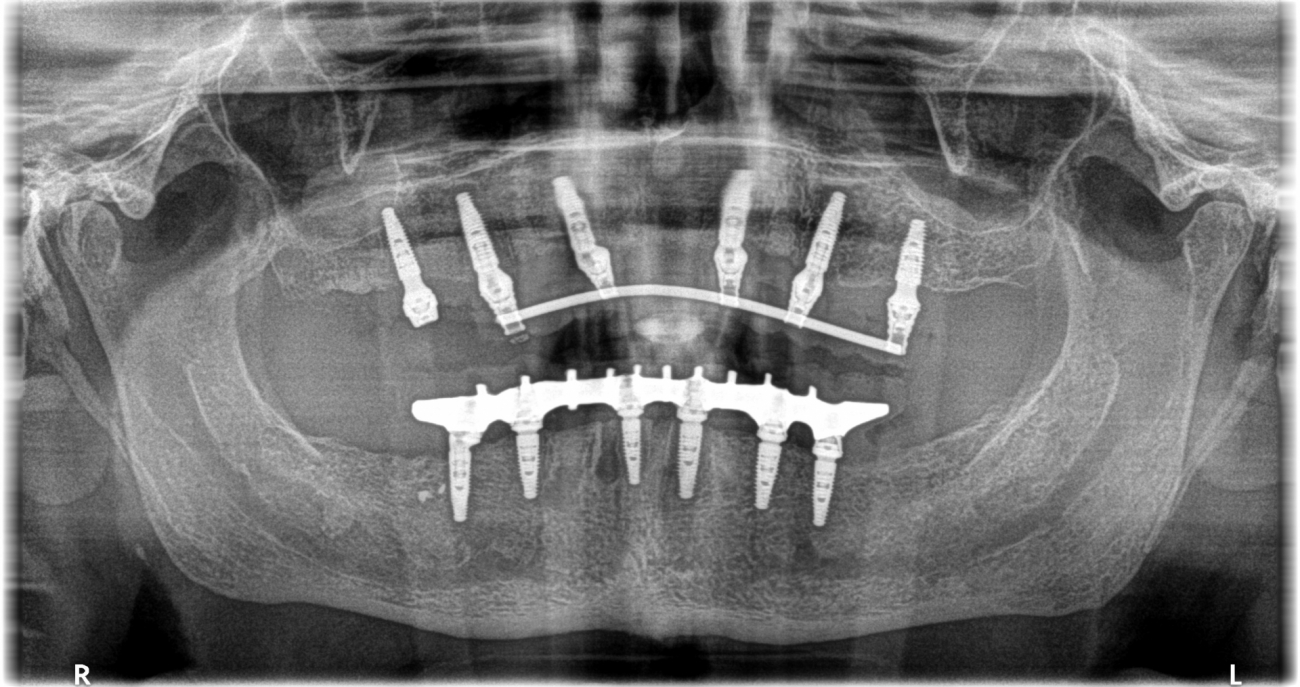

L’implantologia a carico immediato, è una tecnica che permette di posizionare i denti ovvero la protesi fissa, il giorno stesso o al massimo 72 ore dopo il posizionamento degli impianti. Questo è possibile perché gli impianti solidarizzando tra di loro, impediscono la possibilità di micromovimenti, che potrebbero impedire l’osteointegrazione e quindi la loro guarigione.

E’ fondamentale che gli impianti inseriti abbiano un torque sufficiente, ovvero una stabilità primaria all’interno dell’osso di almeno di 35 newton, questa è la condizione essenziale per posizionare i denti sopra gli impianti. Questa tecnica è spesso utilizzata, quando dobbiamo riabilitare con gli impianti un’arcata o entrambe le arcate dentarie di un paziente, in questi casi inseriremo da un minimo di 4 impianti per arcata ad un massimo di 6 impianti, posizionando subito dopo l’intervento la protesi fissa. Questo permetterà agli impianti di lavorare insieme rendendo più facile l’osteointegrazione e quindi una corretta guarigione. Il carico immediato può essere fatto anche nel caso in cui dovessimo inserire un impianto singolo, basterà solamente evitare che il dente abbia contatti in occlusione, che possano creare micromovimenti durante il periodo di guarigione.

Ad oggi questo sistema ci permette nei casi clinicamente idonei, di essere più precisi e sicuri e spesso senza mettere neanche i punti di sutura. Attraverso questa procedura è possibile sapere in anticipo la posizione esatta degli impianti. In quanto tutto è pianificato tramite la Tac al computer prima dell’intervento e su questa pianificazione verrà prodotta una dima chirurgica che ci guiderà nel posizionamento degli impianti, i quali andranno esattamente nella posizione che noi avevamo stabilito in precedenza sul computer. Questa tecnologia riduce sensibilmente l’invasività della chirurgia e crea pochissimo discomfort ai nostri pazienti. Se abiti a Chiesina Uzzanese o dintorni, non esitare a contattarci per prenotare una seduta di implantologia a carico immediato con chirurgia guidata.